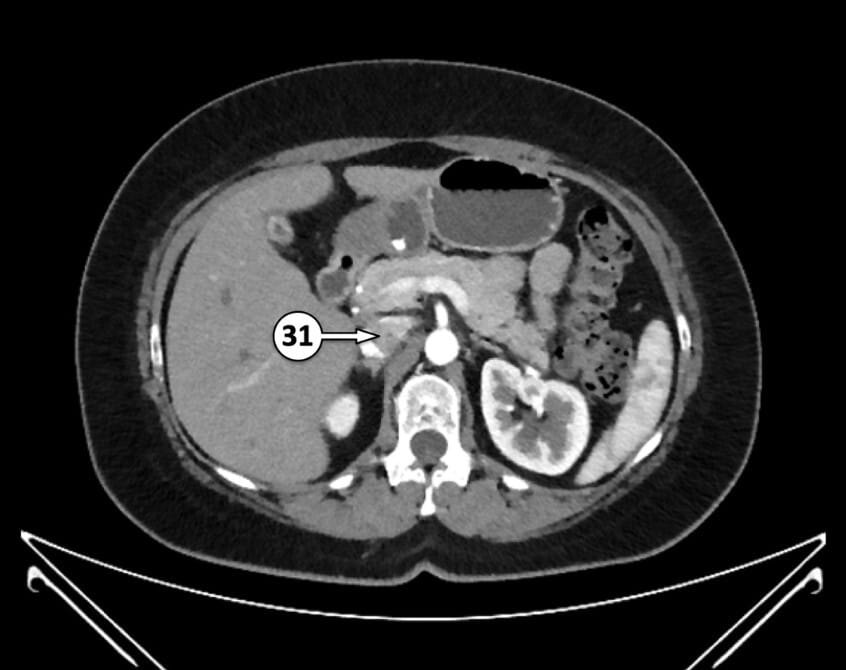

31. suprarenal segment of inferior vena cava